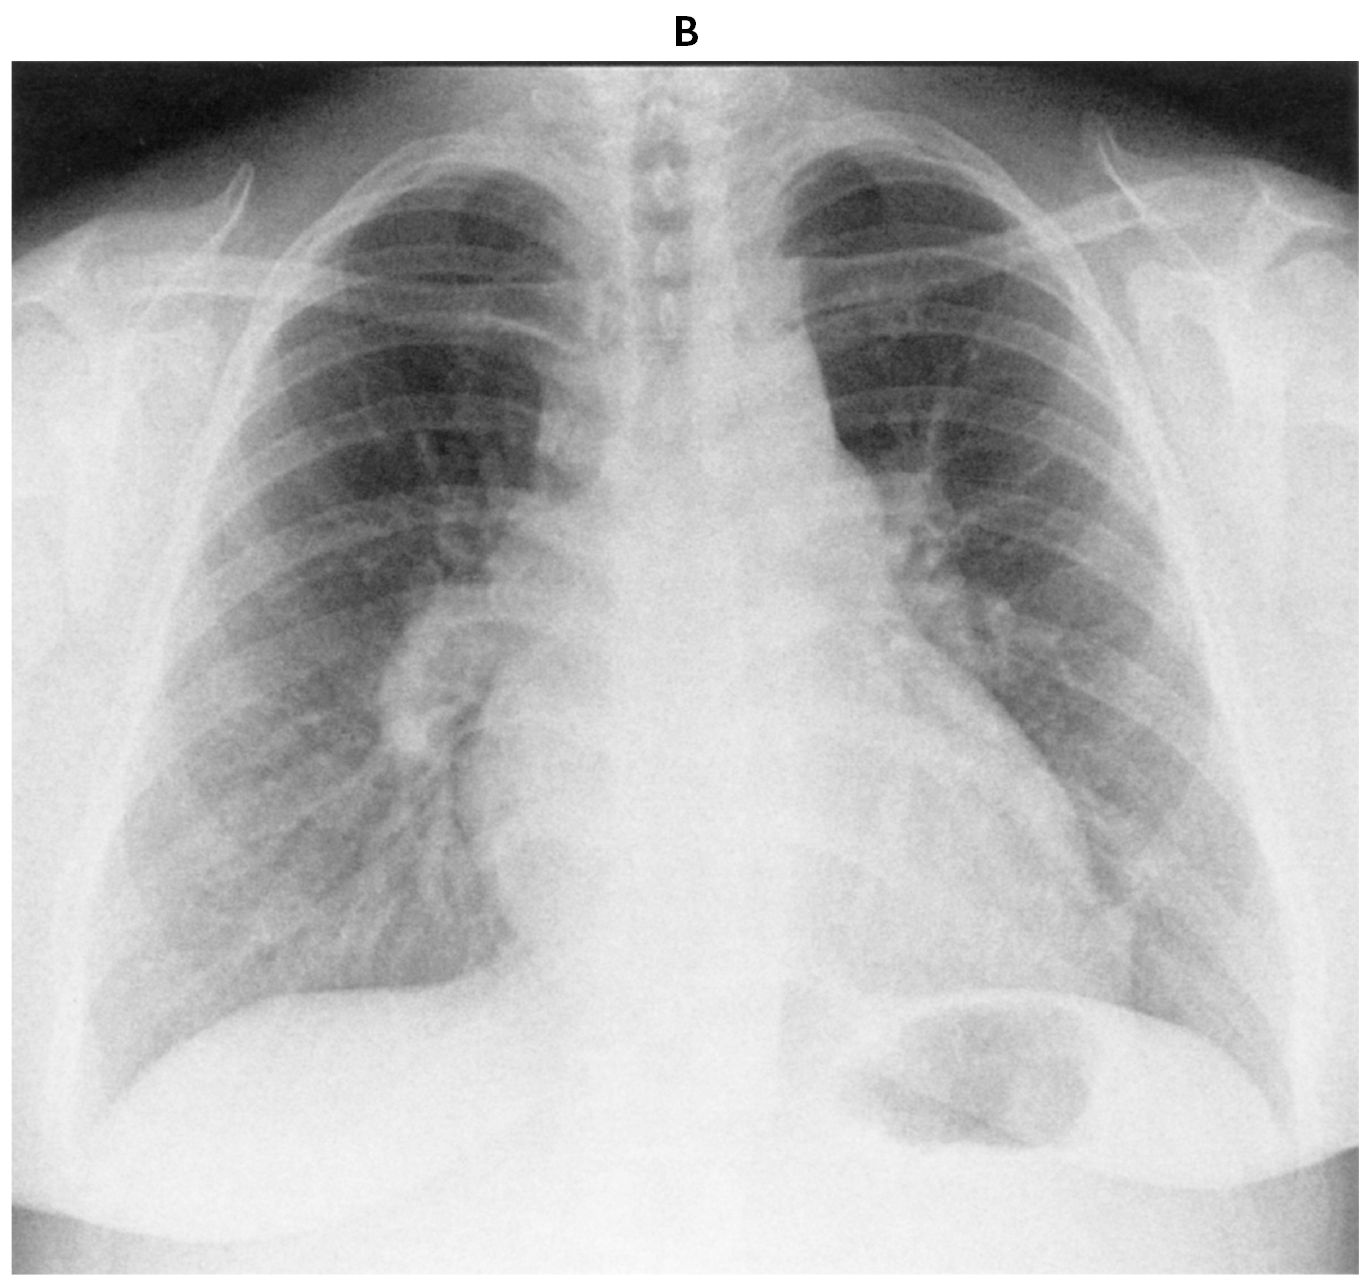

32歳の女性。呼吸困難を主訴に来院した。1か月前から労作時の呼吸困難を自覚していた。徐々に症状が増悪するため受診した。意識は清明。身長170cm,体重88kg。体温36.6℃。脈拍96/分,整。血圧128/68mmHg。呼吸数20/分。SpO2 90%(room air)。眼瞼結膜と眼球結膜とに異常を認めない。頸静脈の怒張を認める。心音はⅠ音正常,Ⅱ音亢進を認める。呼吸音に異常を認めない。腹部はやや膨満。下腿浮腫を認める。受診時の12誘導心電図(A)と胸部エックス線写真(B)とを下に示す。

無料会員登録していただくと、実際の解説をすべて見ることができます。急性の呼吸困難を主訴とする疾患としては,喉頭浮腫,気道異物,自然気胸,気管支喘息,慢性閉塞性肺疾患の急性増悪などの呼吸器疾患,心不全(急性,慢性の急性増悪),肺血栓塞栓症などの循環器疾患が代表的である。この症例では呼吸器感染症と心不全が疑われるが,胸部エックス線写真は肺炎像というよりも両心不全を示唆する所見を示している。診断:心不全(両心不全)(Nohria分類wet and warm) 選択肢考察 ×a 強い呼吸困難,胸痛などにより安静が保てない場合には,血管拡張による前負荷軽減と,交感神経抑制による心筋酸素消費量の減少を目的としてモルヒネを使用する。この症例ではモルヒネが必要となるほどの興奮状態ではない。